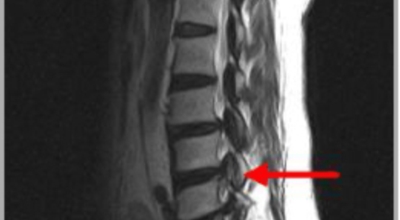

요추관 협착증은 척추 내 신경이 지나가는 통로가 좁아지는 현상으로 기인해서 신경이 눌리면서 이에 따른 여러가지 증상을 유발하는 질환을 의미해요.

허리 협착증은 척추관이 좁아지게 되면서 신경을 압박하게 되어 허리통증과 또한 다리에도 여러가지 증상을 일으키게 되는데, 발생 원인은 주로 노화로 인한 퇴행성 변화가 많았지만 요즈음는 옳지 않은 자세로 오랫동안 앉아있는 사람들이 많아지면서 생기는 경우도 많아졌으며, 선천적인 요인으로 나타나는 경우도 있답니다.

일상생활에서 허리 척추에 무리를 주는 행위가 반복적으로 행해질 경우 허리 뿐만 아니라 주변 근육과 인대의 퇴행이 빨라질 수 밖에 없어요. 허리 협착증의 경우 허리를 뒤로 젖히면 통증이 심하게 나타나지만 허리를 굽히면 척추관이 일시적으로 넓어지는 영향으로 통증이 줄기 때문에 자연스럽게 아프지 않은 자세를 하다보니 허리가 점점 굽는 자세를 만들 수 있어요.